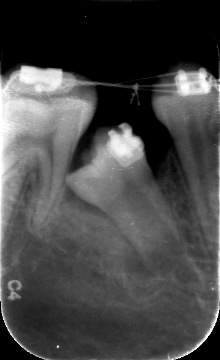

影像片显示右下五远中阻生,靠近于第一磨牙,乳五滞留。

阻生的右下五